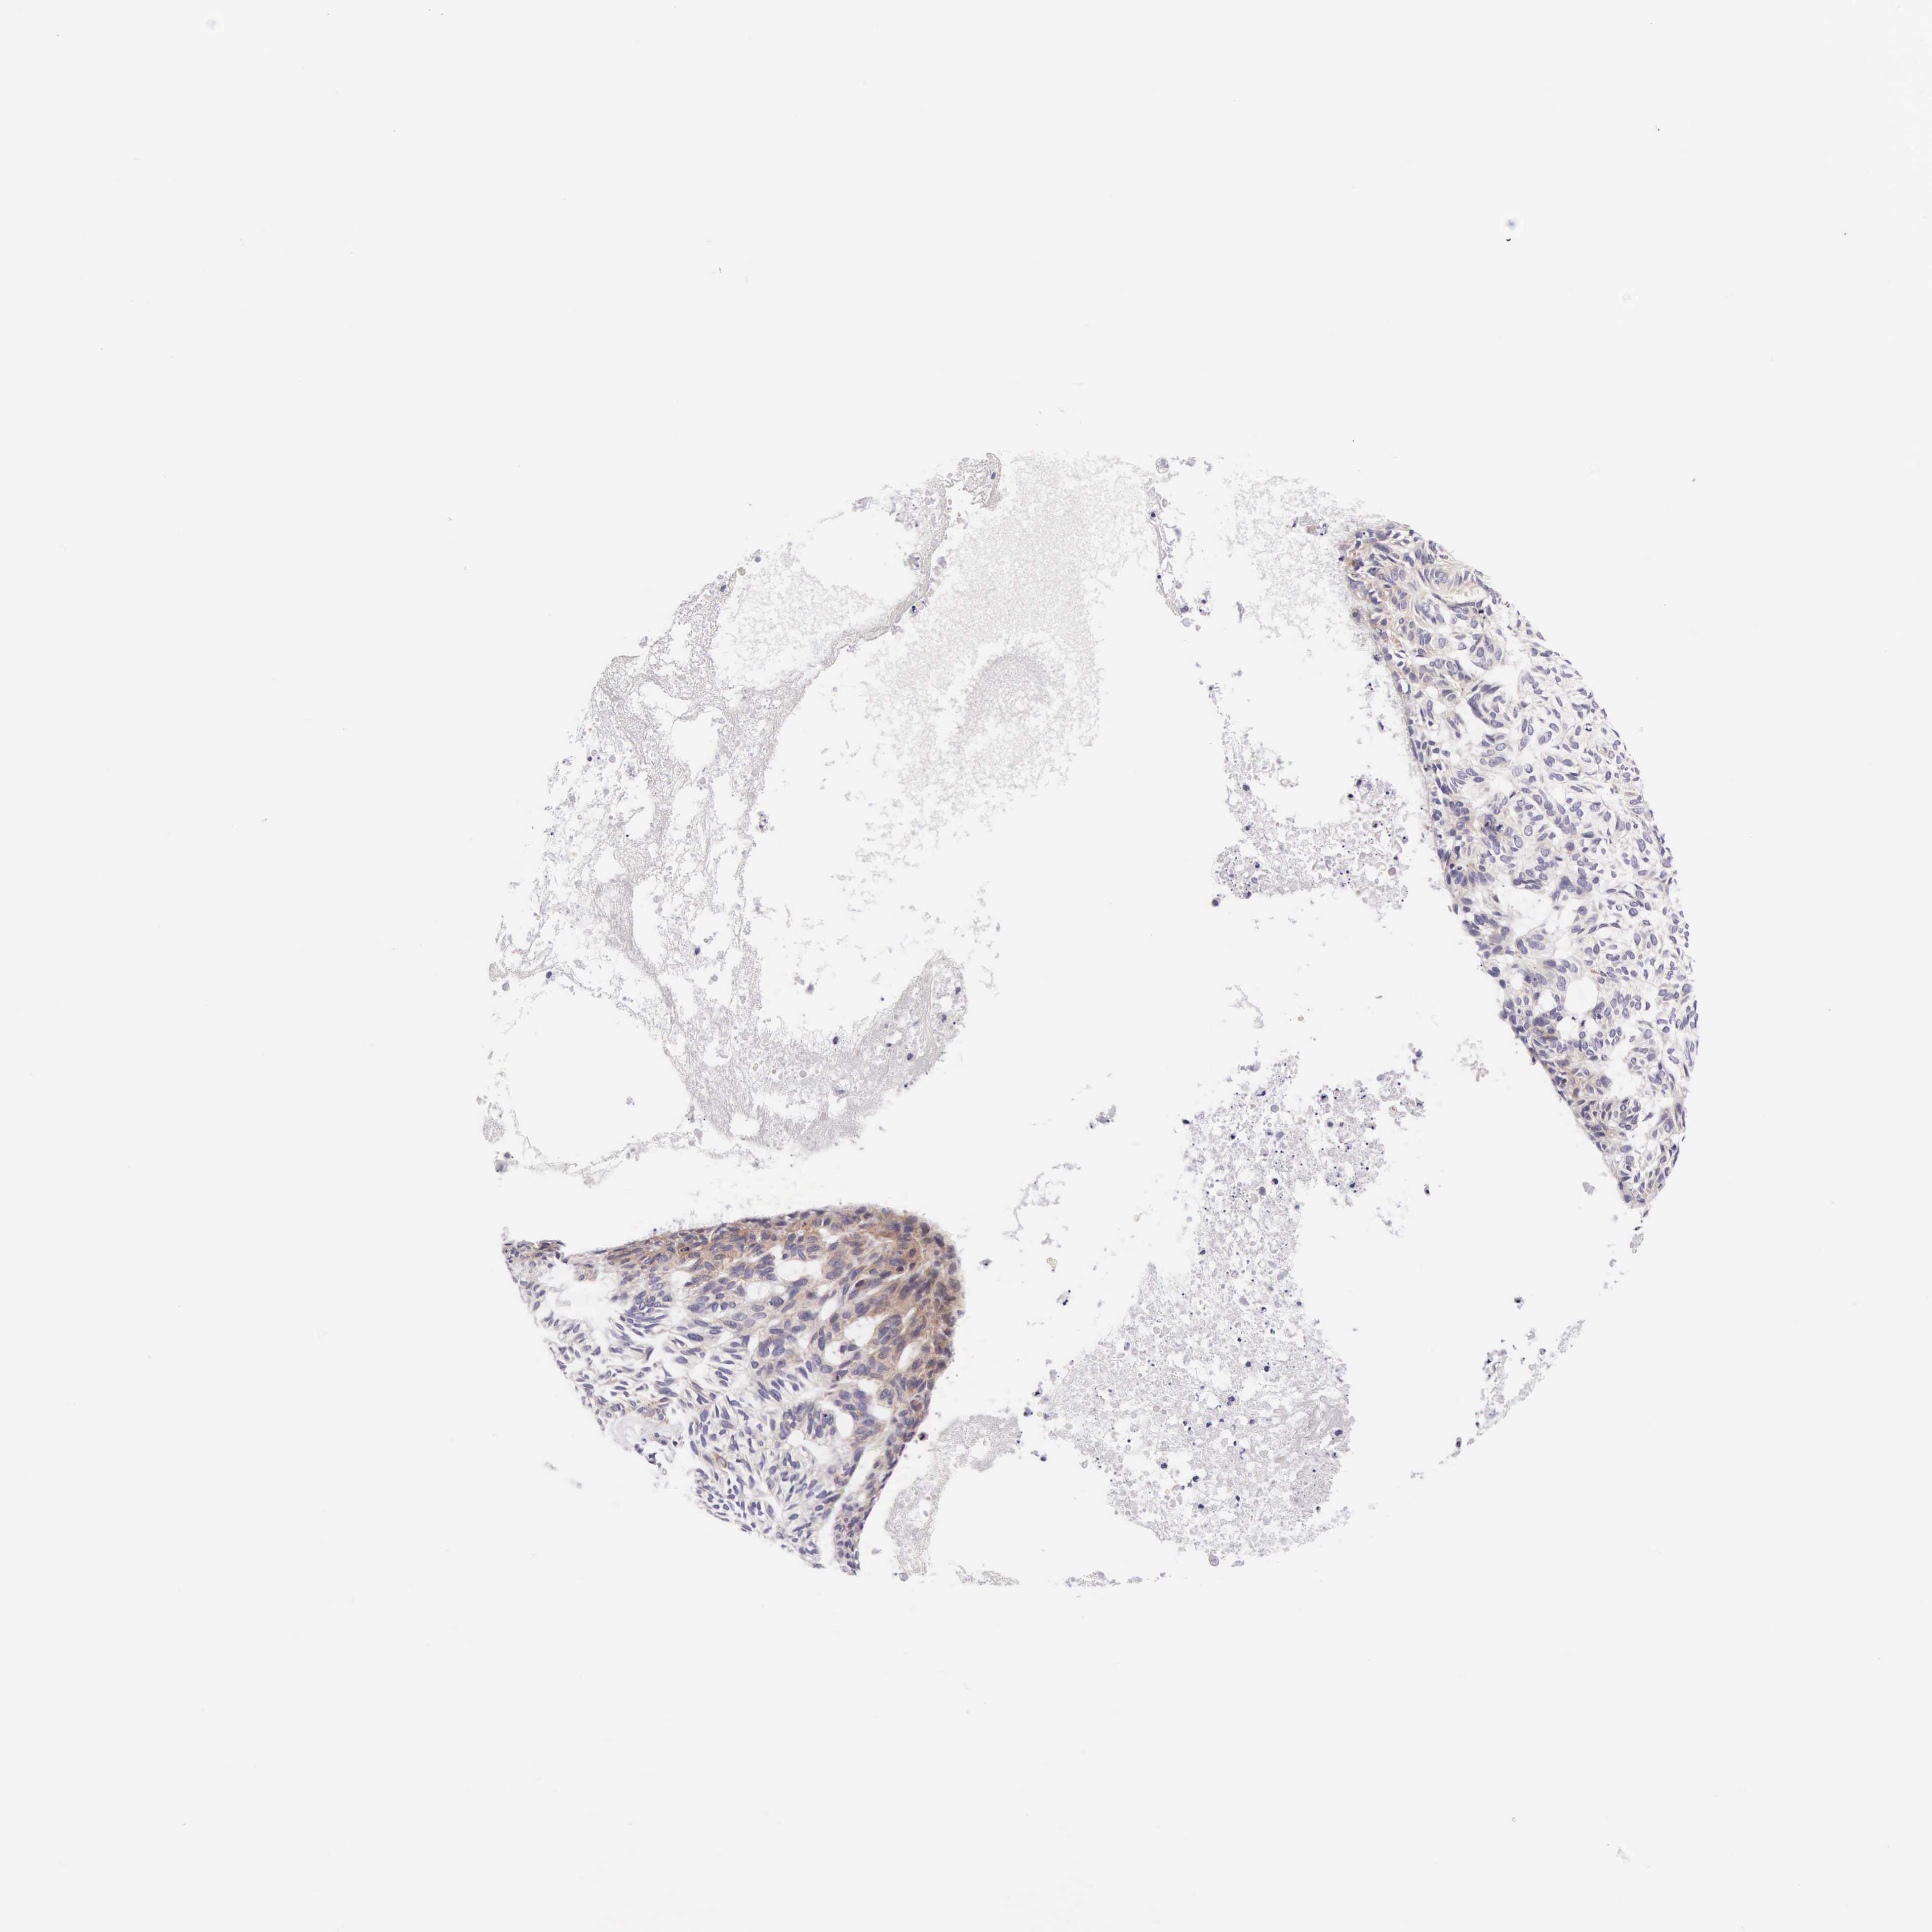

SKIN CANCER - Protein expressioni

A mouse-over function shows sample information and annotation data. Click on an image to view it in a full screen mode. Samples can be filtered based on level of antibody staining by selecting one or several of the following categories: high, medium, low and not detected. The assay and annotation is described here.

Antibody stainingi

Antibody staining in the annotated cell types in the current human tissue is reported as not detected, low, medium, or high, based on conventional immunohistochemistry profiling in selected tissues. This score is based on the combination of the staining intensity and fraction of stained cells.

Each image is clickable and will lead to virtual microscopy that enables deeper exploration of all samples and also displays staining intensity scores, fraction scores and subcellular localization as well as patient and tissue information for each sample.

Antibody HPA000805

Intensity

Strong

Moderate

Weak

Negative

Quantity

>75%

75%-25%

<25%

None

Location

Nuclear

Cytoplasmic/membranous

Cytoplasmic/membranous,nuclear

Squamous cell carcinoma, NOS

Basal cell carcinoma